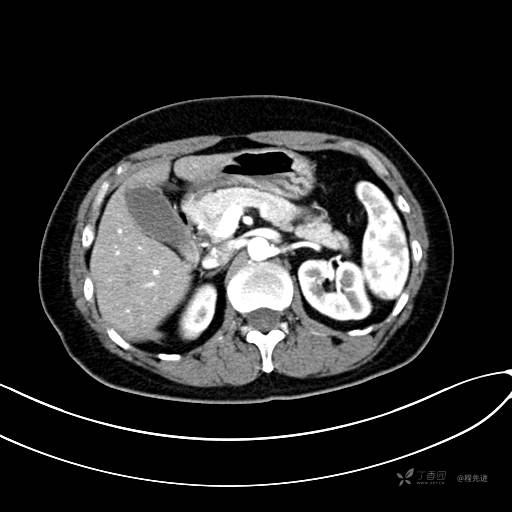

CT增强动脉期